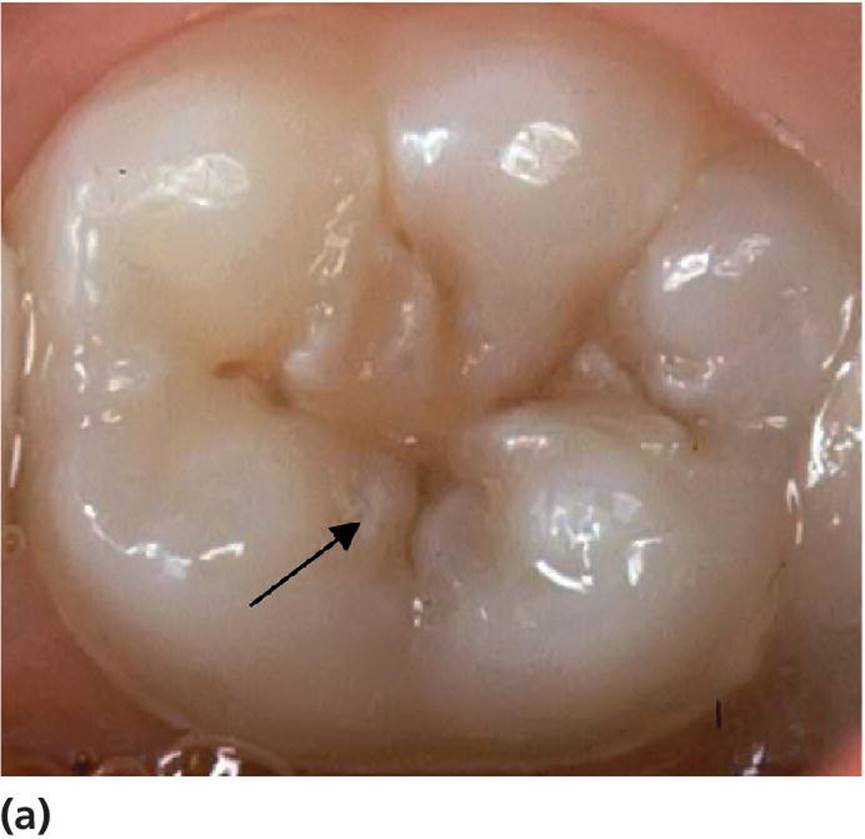

· Active lesions are most frequently seen in erupting and newly erupted teeth in children with other signs of caries activity in the dentition. The discoloration is usually opaque, whitish, or light brownish. Softened enamel at the entrance of the fissure from gentle tactile probing is indicative of an active lesion. When the discoloration also involves obvious loss of continuity of the enamel surface (clinical cavity), bitewing examination frequently reveals a radiolucency in the dentin (Figure 12.5). Many borderline cases can be difficult to diagnose. For these cases, bitewing radiography is a valuable tool for assessing possible dentin involvement (Figure 12.6a,b).

Figure 12.5 A small but obvious occlusal cavity in the central fossa of a permanent first molar (arrow). The borders around the cavity are whitish and rough in texture suggesting an active caries process. There is a shadow from underlying dentin caries. The radiograph reveals a substantial radiolucency in the dentin (arrow).

Figure 12.6 (a) Light brown discolored fissures in a permanent first molar of an 8‐year‐old. The enamel around the central fossa is whitish and there is softened enamel at the entrance of the fissure indicating an active lesion (arrow). (b) The radiograph reveals radiolucency in the dentin (arrow). (c) Dark brown/black discolored fissures in a permanent first molar of a 19‐year‐old with a low caries activity. The fissures are hard on probing indicating an arrested (inactive) lesion.